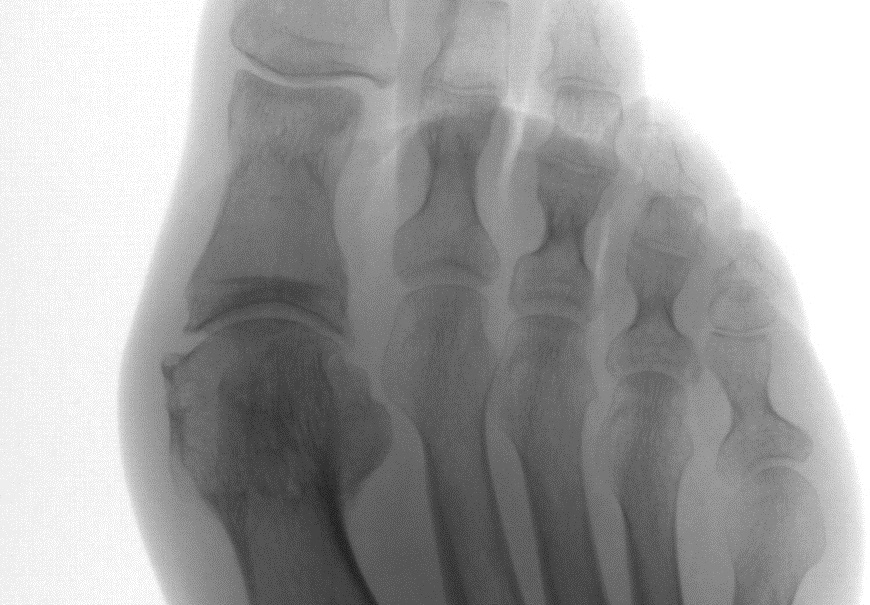

Нарушение формы стопы обусловлено развитием hallux valgus – пресловутой «косточки на стопе», с которой успешно борются хирурги.

Разумеется, выполнены снимки области болезненности. На снимках врачом обнаружен перелом остеофита — костного разрастания, которым организм пытается увеличить площадь контакта в больном суставе.